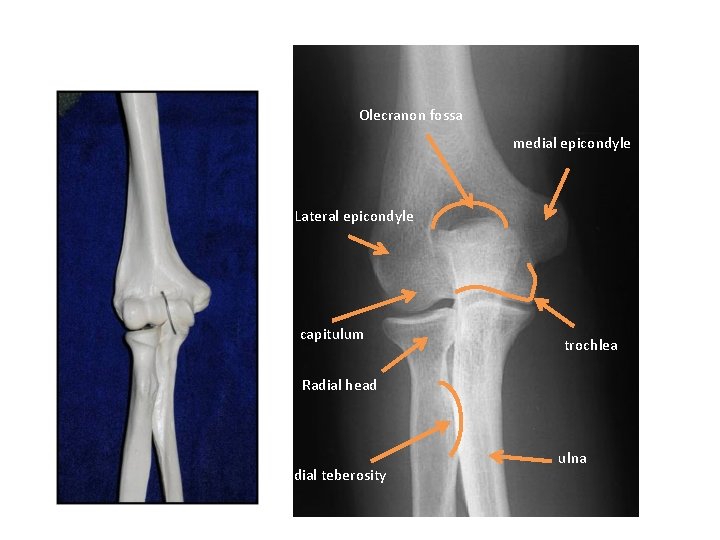

ELBOW

X RAY

Olecranon fossa medial epicondyle Lateral epicondyle capitulum trochlea Radial head Radial teberosity ulna

humerus Coroniod process Olecranon fossa olecranon Radial teberosity Radial head ulna